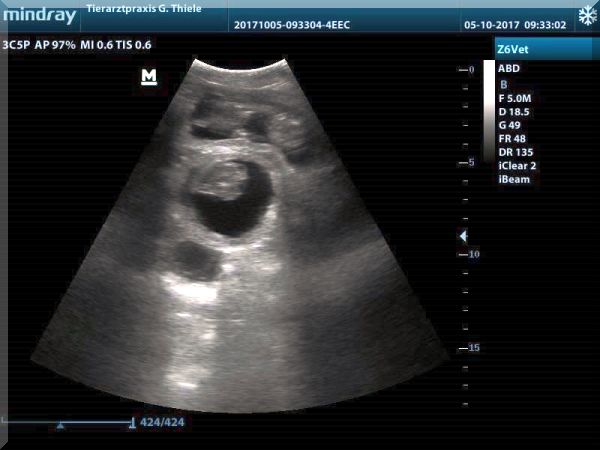

Ultraschall-Bilder von Gloria vom Wieratal

vom 05.10.2017

unser Z-Wurf